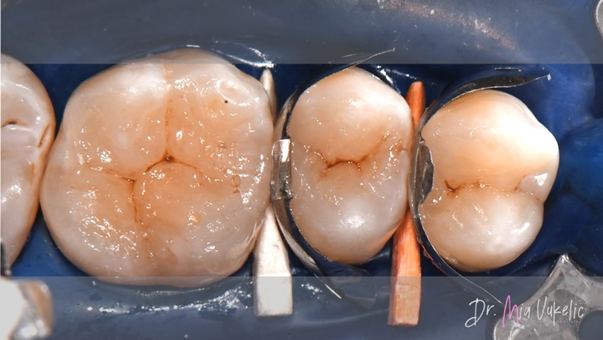

Die Zähne wurden mit Hilfe von Kofferdam und Keilen sorgfältig isoliert. Für die Kavitätenpräparation kam zu Beginn ein zylindrischer Bohrer zum Einsatz. Nach der Entfernung der Restauration wurde das demineralisierte Dentin mit einem Stahlbohrer entfernt. Zum Abschluss der Kavitätenpräparation wurden konvergente Wände in divergente Wände umgearbeitet und die Kavitätenoberfläche mit Diamantpolierern poliert.

Für die Wiederherstellung der Approximalwand kamen Halo™ Matrizen und Ringe (Ultradent Products) zum Einsatz.